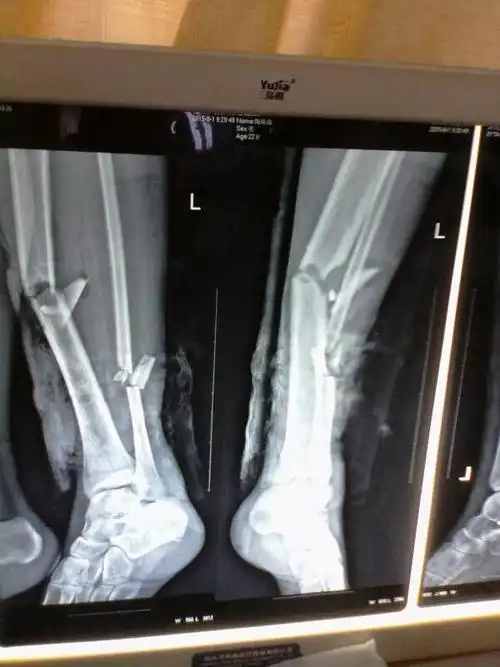

mippo技术治疗胫骨下段骨折